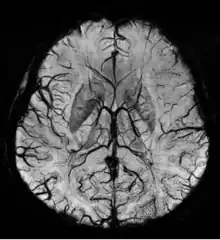

Sturge–Weber disease

An SWI venogram of a neonate with Sturge–Weber syndrome who did not display neurological symptoms is shown to the right. The initial conventional MR imaging methods did not demonstrate any abnormality. The abnormal venous vasculature in the left occipital lobe extending between the posterior horn of the ventricle and the cortical surface is clearly visible in the venogram. Due to the high resolution even collaterals can be resolved.